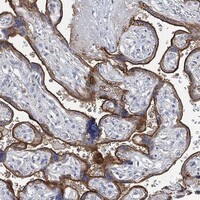

Enhanced - Orthogonal

Antibody staining mainly consistent with RNA expression data across 41 tissues.

HIGH EXPRESSION

Placenta

RNA expression: 63.5 nTPM

LOW EXPRESSION

Tonsil

RNA expression: 8.1 nTPM